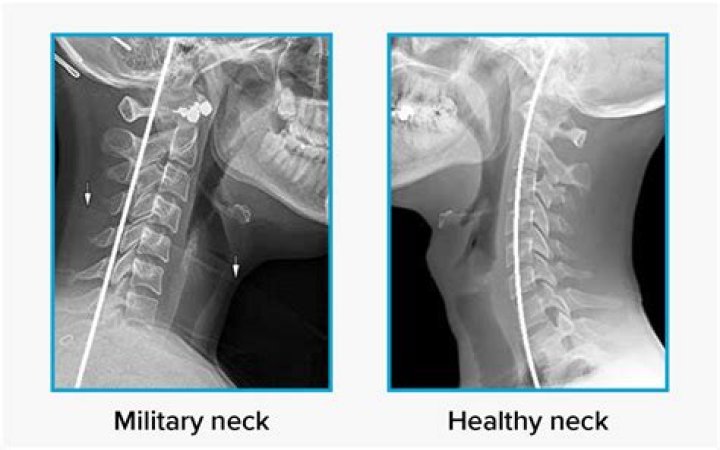

Military neck, or cervical kyphosis, is a rare condition that involves an abnormal curvature of the cervical spine, or neck. It can lead to severe disabil...